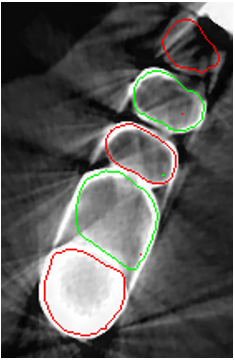

Despite all the appealing features from the contour propagating scheme, level-set methods demonstrate a common limitation, i.e., it is difficult to delineate unclear boundaries (Fig. 2). In a CBCT, the boundaries between the tooth root and the alveolar bone have weak edge characteristics (i.e., a low magnitude of gradient; Fig. 2a) and the presence of severe metal artifacts (Fig. 2b), which hinder the accurate propagation of a contour-based level-set method. Furthermore, level-set methods require tedious manual user interaction to define the initial contour [4, 5, 7], indicating a semiautomated algorithm.

The manual seeded level-set methods [6, 7] demonstrate inferior performances while segmenting teeth with predominant metal artifacts (Table II). The energy-based (i.e., level-set function) algorithmic approach failed while defining an optimum stopping criterion (Fig. 12b). The AJI measures for level-set methods are omitted because the box detectors do not exist in the level-set-based methods. In particular, the low precision and sensitivity values indicate that level-set methods have over-segmented or under-segmented the teeth in many cases (Figs. 12b and 13a). The accuracies of the Mask-RCNN [17] and ToothNet [11] showed comparable performance to the level-set-based methods. The instance segmentation framework successfully detected and segmented the teeth automatically. However, it failed to detect all the teeth regions accurately, which resulted in a degradation of the segmentation performance. Moreover, the performance of the segmentation itself also showed low accuracy owing to the metal artifacts (Figs. 12c and 12d). Figure 13 illustrates the more severe conditions of metal artifacts. The performance of the detection and segmentation processes significantly degraded in ToothNet [11] (Fig. 13b) and Mask-RCNN [17] (Fig. 13c). Conversely, our proposed method outperformed the other state-of-the-art methods (Figs. 12e and 13d); further, the comparison between the PA- and non-PA-based results also demonstrated that the employment of a PA detector significantly improved the proposed architecture (Table II). The superior AJI value clearly shows that successful detection improved the overall performance.